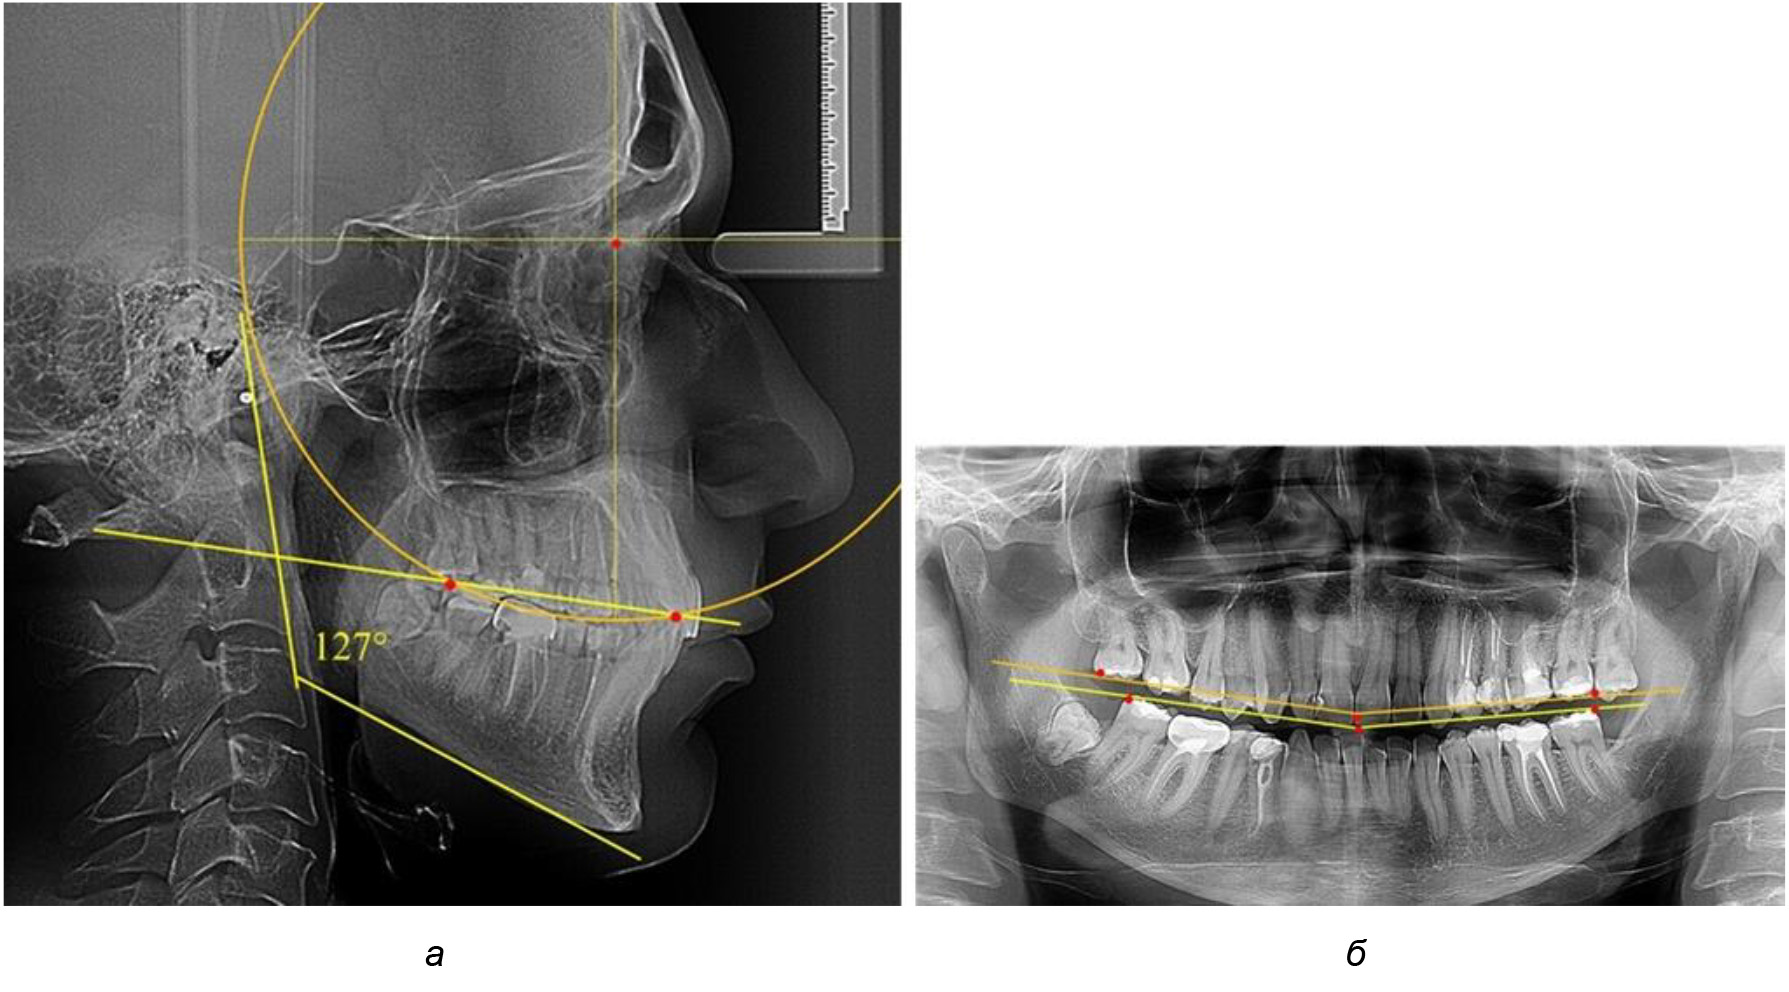

Обращает на себя внимание, что глубина кривой Spee в анализируемой подгруппе практически не отличалась от показателей, полученных у людей с физиологической окклюзией, и составляла (4,23 ± 1,58) мм. Отношение радиуса окружности к сагиттальному размеру окклюзионной линии в среднем по подгруппе составляло 1,623 ± 0,02 и соответствовало числу Фибоначчи.

После лечения пациентов техникой «прямой» дуги, так же как и в 1-й подгруппе, было отмечено увеличение сагиттального размера окклюзионной лини в среднем на (2,38 ± 0,83) мм. Окклюзионная линия практически касалась окклюзионного контура всех жевательных зубов, и отмечалось практически полное отсутствие кривой Spee, так же как и у людей 1-й подгруппы 2-й группы (рис. 6).

Рис. 6. Особенности ТРГ при оптимальной кривой Spee до лечения (а) и после лечения (б) техникой «прямой» дуги

Таким образом, проведенное лечение техникой «прямой» дуги способствует нормализации окклюзионного равновесия и торку передних зубов, однако не соответствует оптимальному окклюзионному статусу, характеризующему физиологическую окклюзию. При этом величина нижнечелюстного угла оставалась на прежнем уровне.